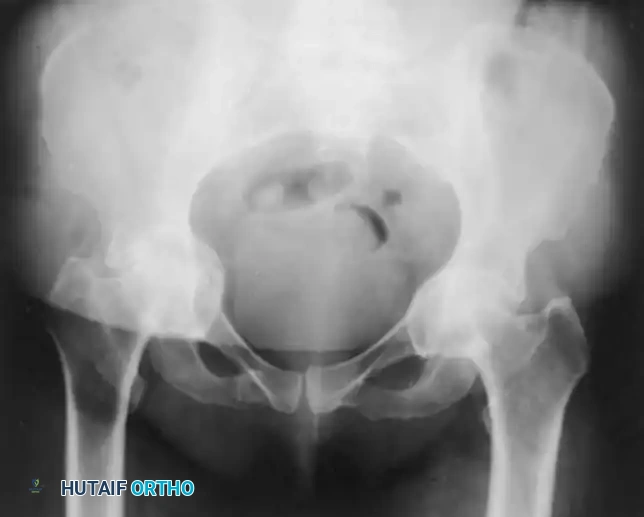

Fig. 7-74 Primary protrusio acetabuli. Otto pelvis in 52-year-old woman. Femoral head has migrated medial to ilioischial (Kohler) line. Hip motion is severely limited.